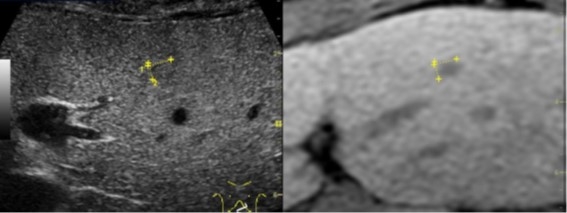

肝細胞癌の内科治療の代表的なものはラジオ波焼灼治療(RFA)と肝動脈化学塞栓術(TACE)です。ラジオ波焼灼治療は超音波では、まず超音波で腫瘍を見ながら肝臓に特殊な針を刺す(穿刺)します。この針は特殊な針で器械に接続されており、スイッチを入れると針の先端2cmないし3cmが60℃〜80℃に加熱されます。これで腫瘍を焼灼して(焼いて)死滅させようとするものです。2cm程度までの早期に見つかった肝細胞癌ではこの治療で十分腫瘍全体を死滅させることが可能で、手術に負けない治療成績を残しています。超音波の画像は見にくい場合があるのですが、当院では最新鋭の医療機器を用いて、CTやMRIの画像と超音波の画像を同期させより確実に目的の腫瘍の中心に針が刺せるようにしています(図6)。

図6:MRI画像(右)とエコー画像(左)を同期させたより確実な肝細胞癌の描出(黄色で示すのが肝細胞癌)